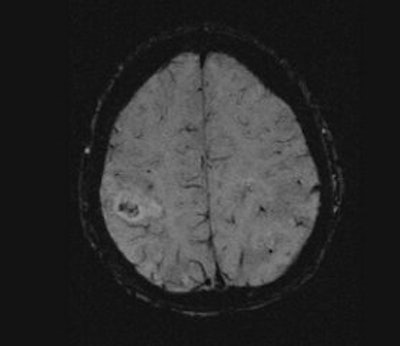

He also presented a trauma case comparing 2D conventional gradient-echo imaging (TE = 20 msec) and SWI. The patient had an accident and suffered subsequent cognitive impairment.

"This is where SWI lets you start seeing very small, almost pixel-like effects, probably microhemorrhages where there may be damage," he said. "Conventional gradient-echo imaging didn’t show any effects, but on the SWI you could see evidence of microhemorrhages and edema (see below). In most cases, you will see something with SWI that you won't see with conventional imaging. It could have significant impact in trauma imaging because you'd like to know what's wrong with them, and whether they are going to get better."

![]() |

| Diffuse axonal injury in trauma. GRE image above; SWI image below. Data was collected on a 1.5-tesla scanner (Vision, Siemens Medical Solutions) with a TE = 40 msec and a resolution of 0.5 mm x 1.0 mm by 2.0 mm. Images courtesy of Dr. Karen Tong, Loma Linda University. |